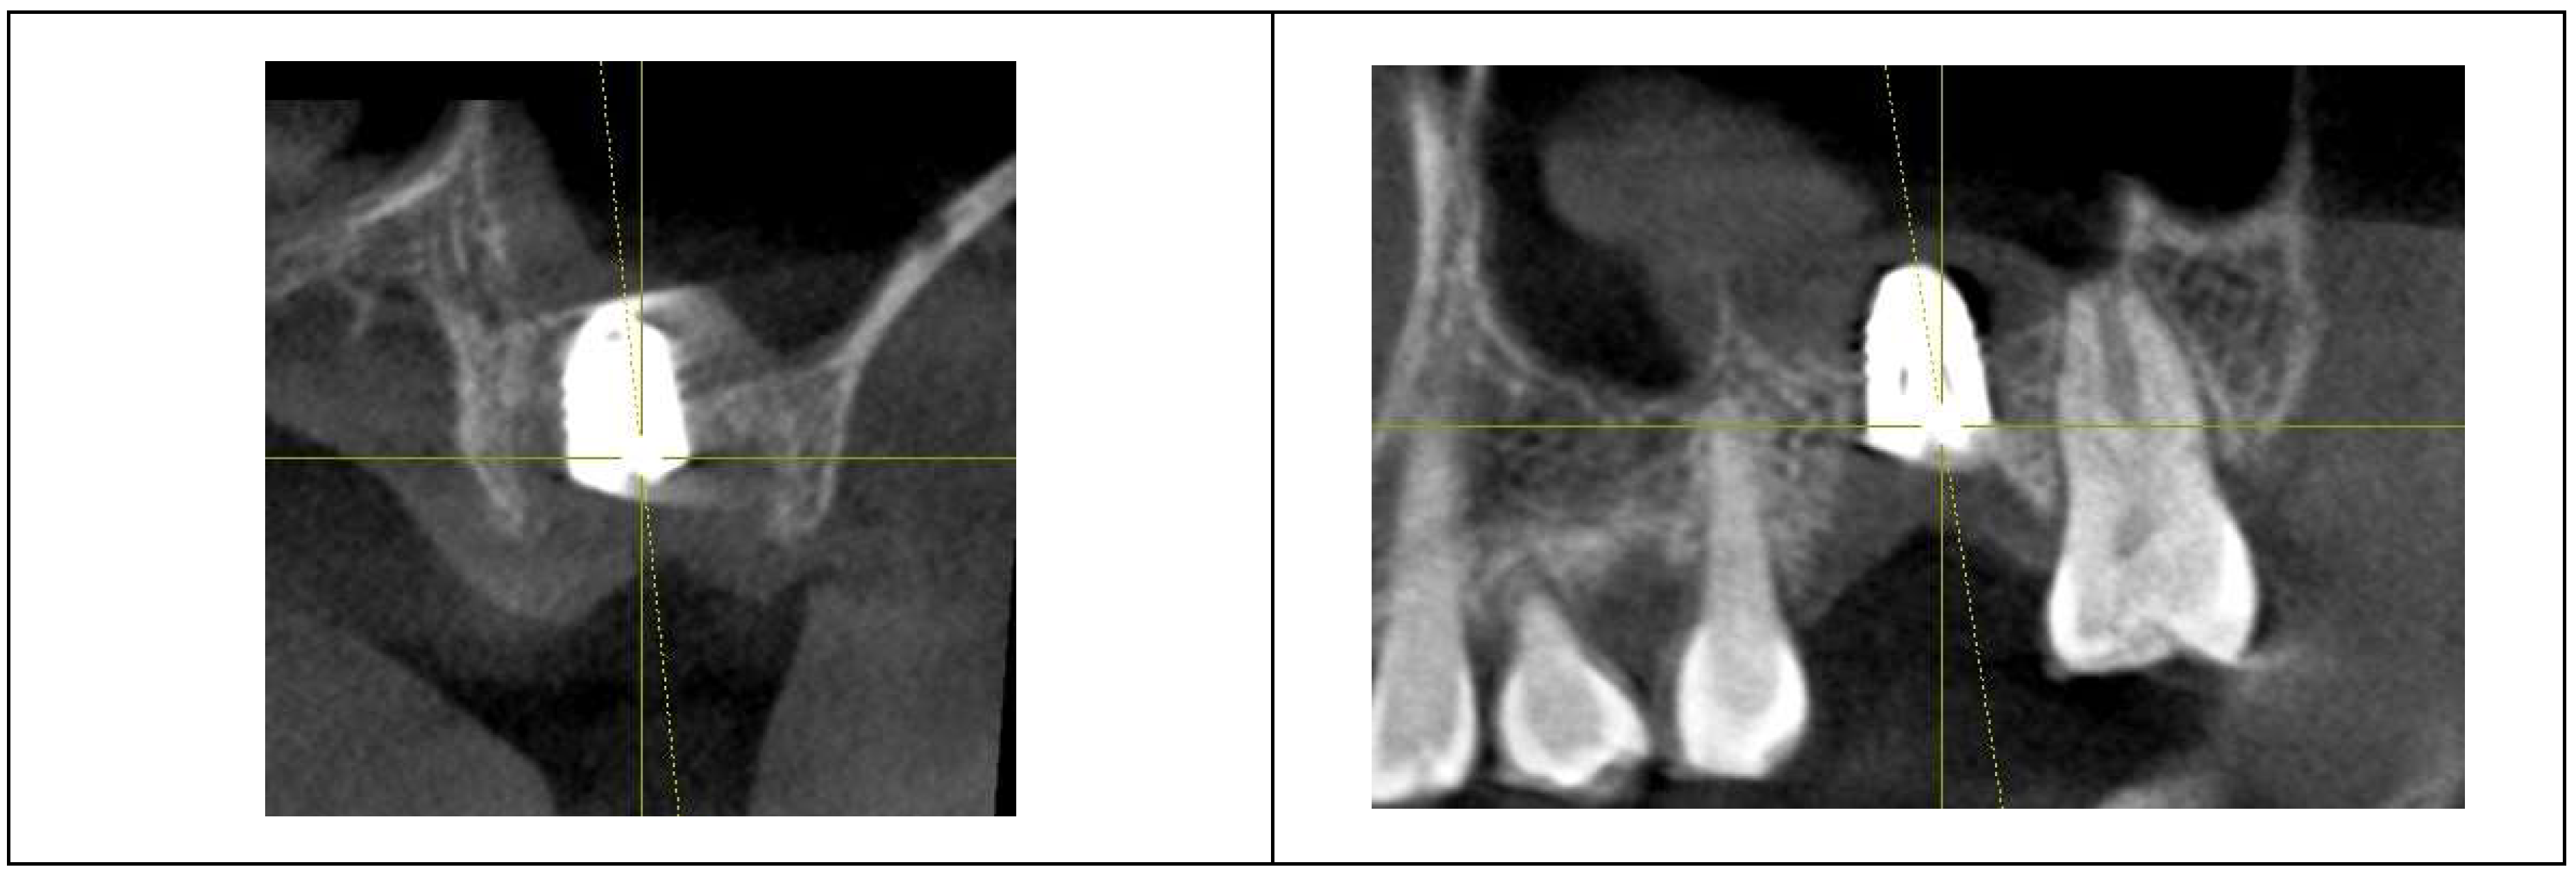

Figure 7 and

Figure 8 illustrate the radiographic changes observed from 2021 to 2024 at the lower right first molar implant site (control site) and the upper left first molar implant site (experimental site), respectively. (

Figure 7,

Figure 8) The clinical photographs taken in 2024 (

Figure 9) depict the final results, showcasing both a stable and natural appearance for both implant sites.

Figure 9.

Clinical images of control and experimental sites post-revision. This figure presents clinical photographs of the control and experimental implant sites following the revision procedure. Both sites exhibit a natural and healthy appearance, indicating successful soft tissue adaptation and restoration aesthetics, taken at 2024.

Following prosthodontic adjustment to reduce CRD, mucositis in the upper left implant resolved, with no BOP and probing depths remaining below 1 mm.

The post-revision evaluation highlights structural changes in peri-implant soft tissue and their impact on implant health.

Figure 10 compares X-rays from October 2021 and July 2024, showing a marked decrease in Crest to Restoration Distance (CRD) after restoration modification. (

Figure 10) The reduction ensured the gap was fully occupied by peri-implant soft tissue, eliminating voids. This suggests that maintaining CRD within a critical range is essential for a stable biological seal, reinforcing the soft tissue barrier against bacterial infiltration.

Figure 10.

Comparison of X-rays taken in October 2021 and July 2024 after the restoration revision, demonstrating a decrease in the CRD. When the CRD is maintained within the critical range, it can be inferred that the gap space is occupied exclusively by peri-implant soft tissue, without voids, and the GRD can be represented as Soft Tissue Thickness (STT).

These findings underscore the importance of CRD optimization in implant restoration and the need for histologic evidence to further validate its role in peri-implant soft tissue stability.